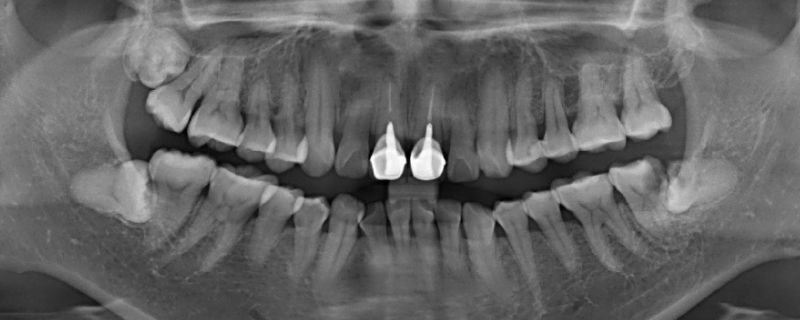

最佳答案冠周在牙冠周围,冠指牙冠,就是牙齿暴露出来的部分,周是周围的意思,综合就是牙冠周围的意思。冠周炎一般是指智齿牙冠周围软组织发生非特异性炎症,如果发生身体不适的症状,应及时到医院就诊。冠周炎考虑是经常挑食、偏食,可能会使身体摄入的营养元素不足,导致全身抵抗力下降,使细菌在牙冠周...

冠周在牙冠周围,冠指牙冠,就是牙齿暴露出来的部分,周是周围的意思,综合就是牙冠周围的意思。冠周炎一般是指智齿牙冠周围软组织发生非特异性炎症,如果发生身体不适的症状,应及时到医院就诊。冠周炎考虑是经常挑食、偏食,可能会使身体摄入的营养元素不足,导致全身抵抗力下降,使细菌在牙冠周围繁殖,出现牙龈肿胀、疼痛的情况。